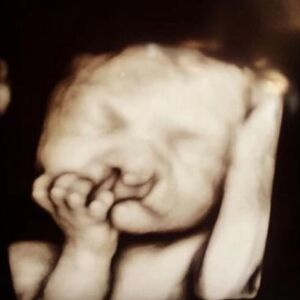

Kod žene koja je u valjevskoj bolnici radila abortus 23. avgusta, a potom joj je zbog sepse sutradan izvađeno slepo crevo izolovana je veoma retka bakterija raoultella planticola i ova pacijentkinja je 27. slučaj u svetu sepse izazvane tom bakterijom, kako je rečeno lekarima u Valjevu, nezvanično saznaje Kurir.

- Ženi od 27 godina je na odseku konzervativne ginekologije Zdravstvenog centra Valjevo u sredu, 23. avgusta urađen legalni prekid trudnoće, što znači da je trudnoća bila manja pod 10 nedelja. A već nakon sat vremena ona je dobila visoku temperaturu, počela je da povraća žalila se na malaksalost. Odmah je urađena hemokultura, skener male karlice, uzeti svi brisevi (vaginalni, cervikalni i urinokultura), kompletna biohemija, kao i ginekološki ultrazvuk koji nije ukazivao na povredu materice nakon intervencije. Konsultovan je infektolog, pulmolog i kardiolog, ostavljena je na opservaciji tu noć, da bi u četvrtak ujutru tražene dodatne konsultacije, koje nisu razjasnile uzrok visoke temperature koja nije spadala, te je žena popodne istog dana prebačena u odeljenje intenzivne nege radi daljeg praćenja - priča izvor Kurira.